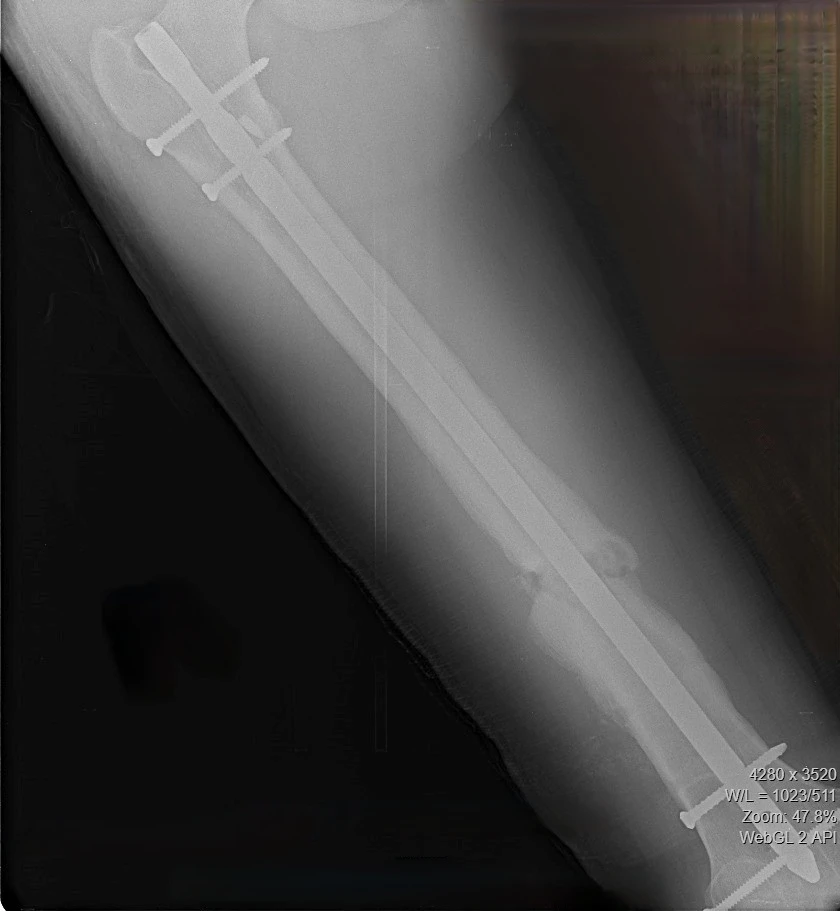

17‑летний Николай поступил к нам с осложнением после операции по поводу перелома бедра. Ранее ему был установлен интрамедуллярный штифт – для фиксации отломков кости с возможностью ранней нагрузки на конечность. Но прежде, чем перелом консолидировался, штифт сломался.

Врачам нужно было найти новое, более подходящее решение, при этом избежать травматичного открытого доступа и обойтись без больших разрезов. Задачу усложнял сломанный внутри кости штифт. Специального серийного устройства для его удаления малоинвазивным способом не существует. Чтобы пройти 40 сантиметров по костномозговому каналу, захватить и извлечь фиксатор, наши специалисты создали свою систему на базе имеющего набора проводников и экстракторов. Тщательное предоперационное планирование принесло желаемый результат в ходе вмешательства.

После успешного удаления прежней конструкции пациенту установили новую надежную систему - с учётом предыдущего опыта. Для этого понадобилось несколько небольших разрезов (не более 2 см). На второй день после операции Николай передвигался по отделению с помощью костылей, уже нагружая оперированную конечность. Сейчас он внимательнее прислушивается к рекомендациям, от выполнения которых зависит благополучие восстановительного периода.